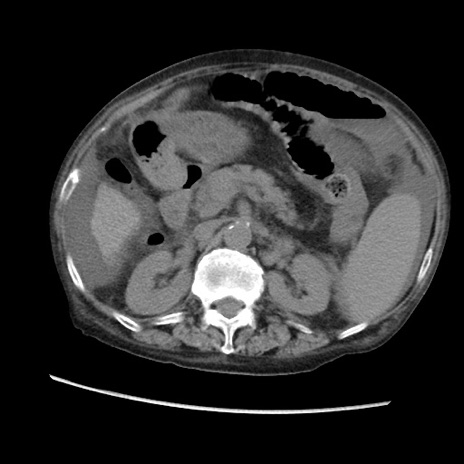

症例31(横断像)

【症例】80歳代 女性

【主訴】腹部膨満感

【現病歴】他院にて肝硬変にてフォロー中。1週間前から便秘、腹部膨満感、臍部腫瘤あり受診となる。

【既往歴】肝硬変

【身体所見】腹部膨隆あり、皮膚変化なし、疼痛なし。

【データ】WBC 4600、CRP 0.25